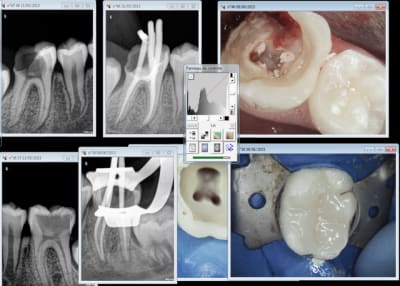

Etonnamment non. Ca arrive de temps en temps. Ici 9 ans.